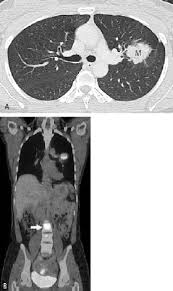

Stages Of Lung Cancer Explained Health Com from imagesvc.meredithcorp.io According to statistics, while lung cancer rates tend to decrease in men, they have increased for women in recent years. It's important to note, however, that the typical symptoms of lung cancer are less likely to be present with lung adenocarcinoma, and currently the most common symptoms are fatigue and shortness of breath with exercise (that can easily be dismissed as due to age or inactivity). Lung cancer is a malignant tumor that develops with uncontrolled and abnormally proliferating altered cell groups, in the lung tissue. Because these tumors usually grow in the periphery of the lungs, far from the large airways, they're less likely to result in a cough. Some of the most common are horner's syndrome, superior vena cava syndrome, and paraneoplastic syndrome. 11 cancer symptoms women shouldn't ignore. lung india: In addition to providing unique insight on what it's like to battle and live with the disease, each story also provides reasons to be hopeful about the future of lung cancer research. This pressure causes some of the signs and symptoms of cancer.

Lung Cancer In Women Clinics In Chest Medicine from els-jbs-prod-cdn.jbs.elsevierhealth.com It's important to note, however, that the typical symptoms of lung cancer are less likely to be present with lung adenocarcinoma, and currently the most common symptoms are fatigue and shortness of breath with exercise (that can easily be dismissed as due to age or inactivity). In addition to providing unique insight on what it's like to battle and live with the disease, each story also provides reasons to be hopeful about the future of lung cancer research. What are the symptoms of lung cancer? This pressure causes some of the signs and symptoms of cancer. Persistent cough that lasts three weeks or more A cancer can grow into,or begin to push on nearby organs, blood vessels, and nerves. Signs and symptoms of lung cancer typically occur when the disease is advanced. The most common symptoms of lung cancer are: